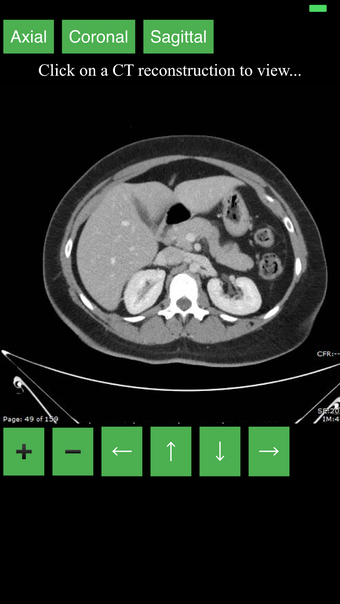

هذا تطبيق فريد من نوعه، تم تطويره من قبل مجموعتنا، لغرض توفير طريقة بسيطة ومفيدة لتعلم تشريح الجسم بالمقطع العرضي.

نقدم أفضل طريقة لتعلم هذا الموضوع، باستخدام جهاز تصوير تشخيصي (CT). نحن نحاول جعل عملية التعلم سهلة وممتعة قدر الإمكان، باستخدام نموذج ثلاثي الأبعاد للجسم البشري.

ما هو CT؟

هذا نوع من التصوير الذي يستخدم أشعة الأشعة السينية لعرض داخل الجسم وبناء صورة للأعضاء والعظام. هذا مفيد للكشف عن الأمراض والإصابات، وأيضًا لمساعدة في فهم تشريح الجسم.